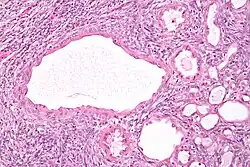

| Micrograph of a cystic nephroma (left of image). Normal kidney is seen on the right. H&E stain. | |

A cystic nephroma, also known as multilocular cystic nephroma, mixed epithelial stromal tumour (MEST) and renal epithelial stromal tumour (REST),[1] is a type of rare benign kidney tumour.

The characteristics of cystic nephromas are:

- Cysts lined by a simple epithelium with a hobnail morphology, i.e. the nuclei of the cyst lining epithelium bulges into the lumen of the cysts,

- Ovarian-like stroma that has a:

- Spindle cell morphology, and has a

- Basophilic cytoplasm.

Micrograph of a cystic nephroma. H&E stain.